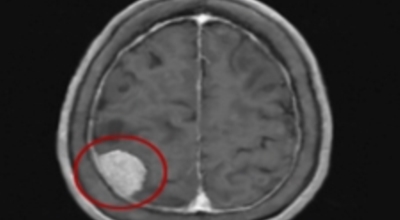

가장 흔한 뇌종양은 수막종이며 종양의 크기나 위치에 따라 수술이 필요하지 않을 수 있지만 청각 신경초종은 이명을 발생시킬 수 있다고 하며 심한 경우 안면 마비, 경련 및 통증을 발생시킬 수 있지만 뇌종양은 생존을 좌우하게되는 교모세포종 문제가 뒤늦게 생기는 것으로 주의가 필요한 이유이예요.